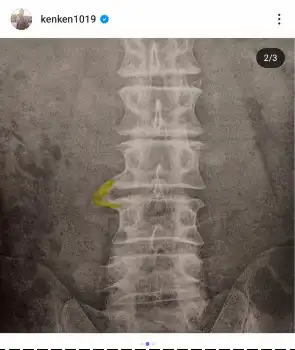

俳優の金子賢(48)が5日、自身のインスタグラムを更新し、「腰椎椎間板症慢性腰痛」と診断されたことを明かした。

3枚のレントゲン画像を投稿し、「あまりにも腰が痛く大学病院で診てもらいました。診断結果は『腰椎椎間板症慢性腰痛』」と報告。「そして『治りません』と、『え?何でですか?』と尋ねると『加齢です、少し良くする事は出来ますが』と言われ複雑な中に加齢によるモノだから治らないと言う言葉に諦めがつき一生付き合って行くものだと気持ちを切り替えました」と医師の言葉を振り返りつつ、前向きな思いをつづった。

「ただ骨と骨が今くっ付き始めてていくつか固まるそうです、腰は動きにくくなりますが痛みは無くなるそうです『10年後』」と明かし、「身長も縮むらしい まあ183あるから180まではセーフとしましょう」とユーモアを交えて心境。